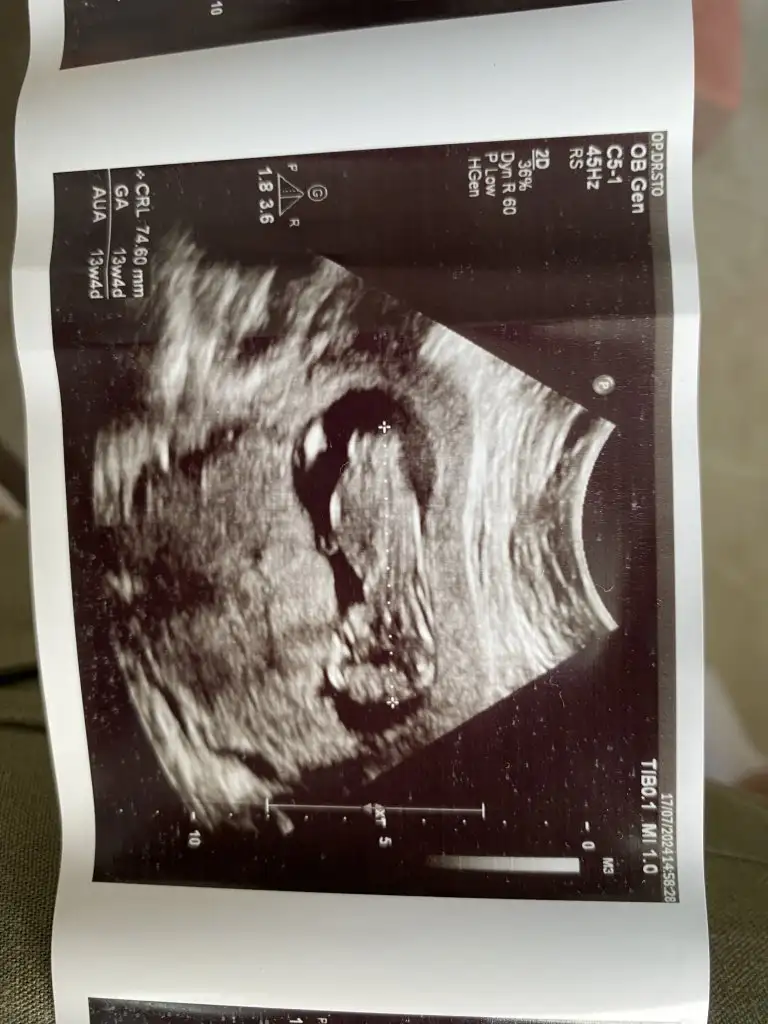

Kızlar öncelikle sağlıkla gelsin bebişlerimiz. Ben cinsiyetle alakalı bir şey sormak istiyorum. Baştan beri kız hissediyorum ilk bebegim ve 3 kez rüyamda kız gördüm. Hatta üçüncüsü çok netti suratını bile çizebilirim. Ama iki doktora gittim ikisi de erkek dedi 13-14. Haftada falandık sanırım. Şuan 16 olmak üzere. Acaba yanılma ihtimalleri var mı ben hala kız oldugunu hissediyorum rüyalardan dolayı kafam çok karışık.

Yanılma olabilir canım ben 12 haftada Medical park Keçiören hastanesinde çok iyi bi doktora gittim ve kesin erkek dediler ama ben hep kız hissediyorum hiç inanmadım 15.ve 17 haftada devlet hastanesine gittim ve bu bebek kız dediler kesinleşti kız olduğu Allah gönlüne göre versin inşallah